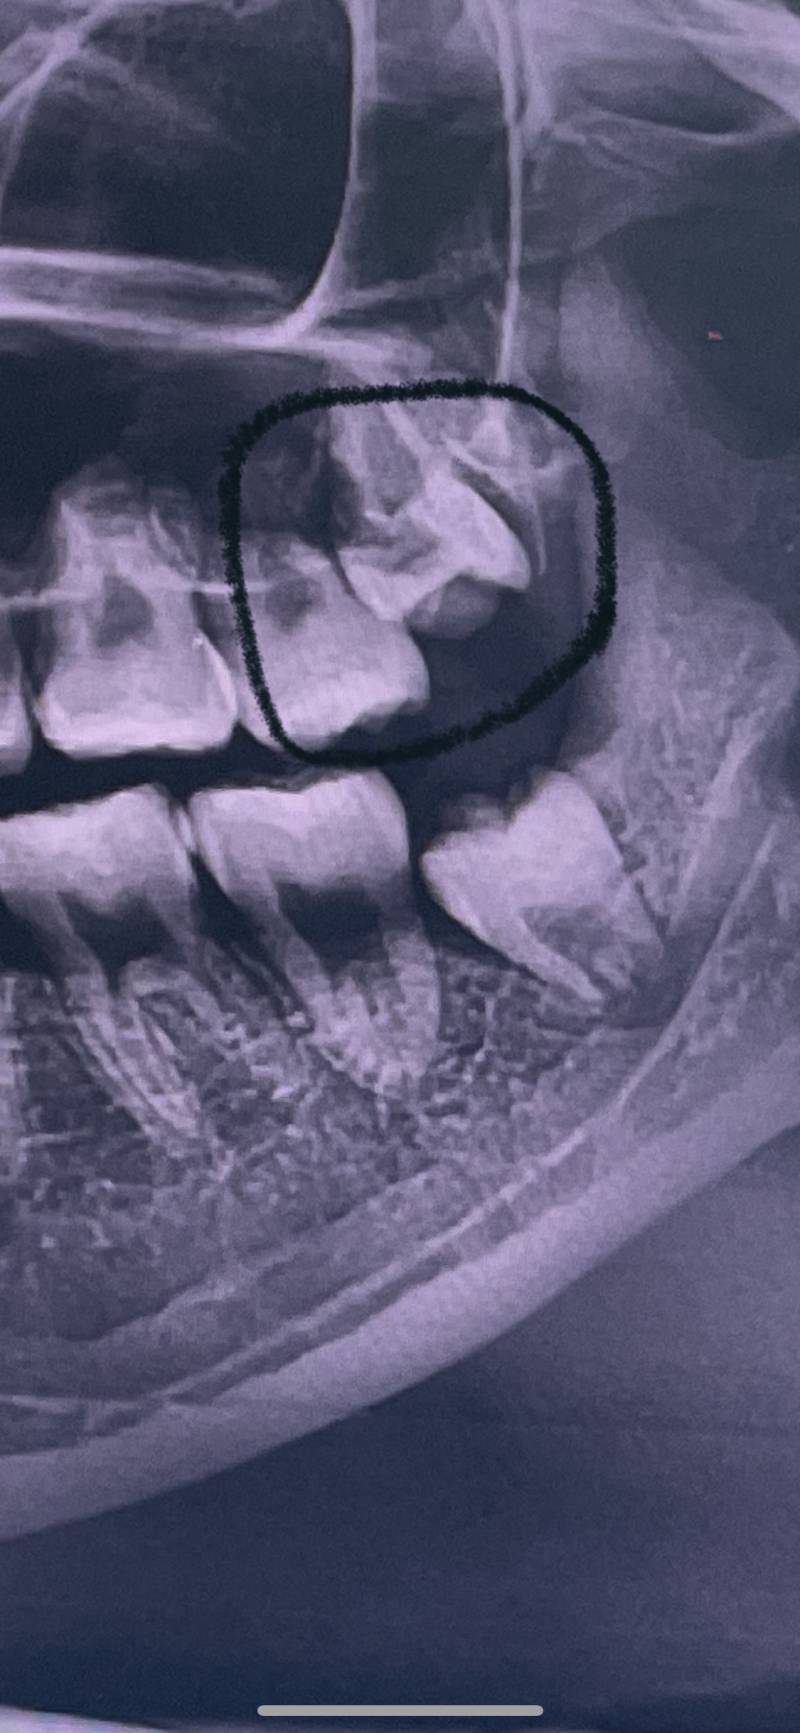

이건 6개월전에 찍은거고 지금 동그라미 친 이빨이 좀 났거든?? 저거 매복일까..? 좀 아픔 ㅠㅠ

어우 뽑아야겠다.. 다나온거 아니면 어차피 째야할걸..

하~~ 6개월전에 뽑은것도 매복이었는데ㅠㅠㅠ

지금 점처럼 보일정도로 약간 났는데 얼마나 났을때 뽑아야돼??ㅠㅠ

치과에서 뽑으라거 하면 뽑아야지.. 잘 못 하면 아프고 잇몸 염증생겨ㅠㅠ

웅웅 나도 매복 사랑니 4개 다 뺏어서 마음 이해해...힘내ㅠㅠ